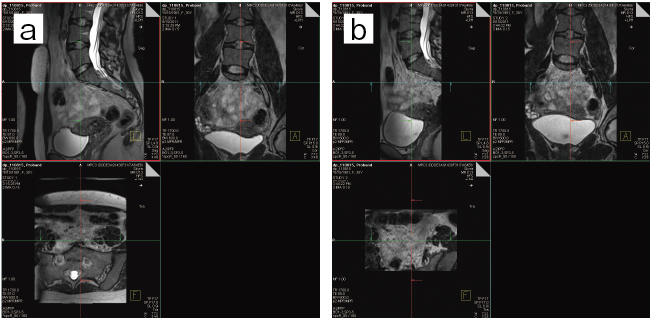

●Higher image quality

体幹部の拡散強調画像のひずみは,局所励起を用いることで低減され,子宮体がんや頸がんの広がり・存在・良悪性診断の精度向上に期待されています。また,近年の3D撮像技術に代表される“syngo SPACE”とsyngo ZOOMitを組み合わせることで,高いB1均一性を担保し,対象領域外(腹壁の体動や血管の流れ)からのモーションアーチファクトも低減するため,パラメトリウムへの広がり診断や所属リンパ節診断に高い期待が寄せられています(図3)。

図3 従来法:9min(a),ZOOMit:6min(b)